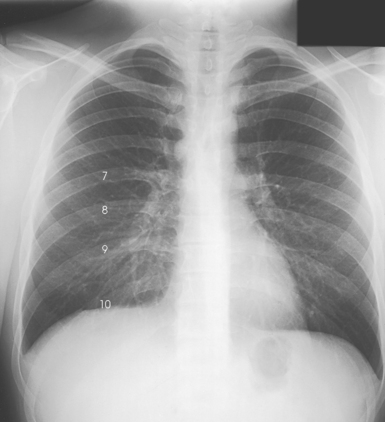

Fig. 10-30 Expiration in the same patient as in Fig. 10-29 (posterior rib numbers).

Structures shown: PA projection of the thoracic viscera shows the air-filled trachea, the lungs, the diaphragmatic domes, the heart and aortic knob, and, if enlarged laterally, the thyroid or thymus gland (Fig. 10-32). The vascular markings are much more prominent on the projection made at the end of expiration. The bronchial tree is shown from an oblique angle. The esophagus is well shown when it is filled with a barium sulfate suspension.